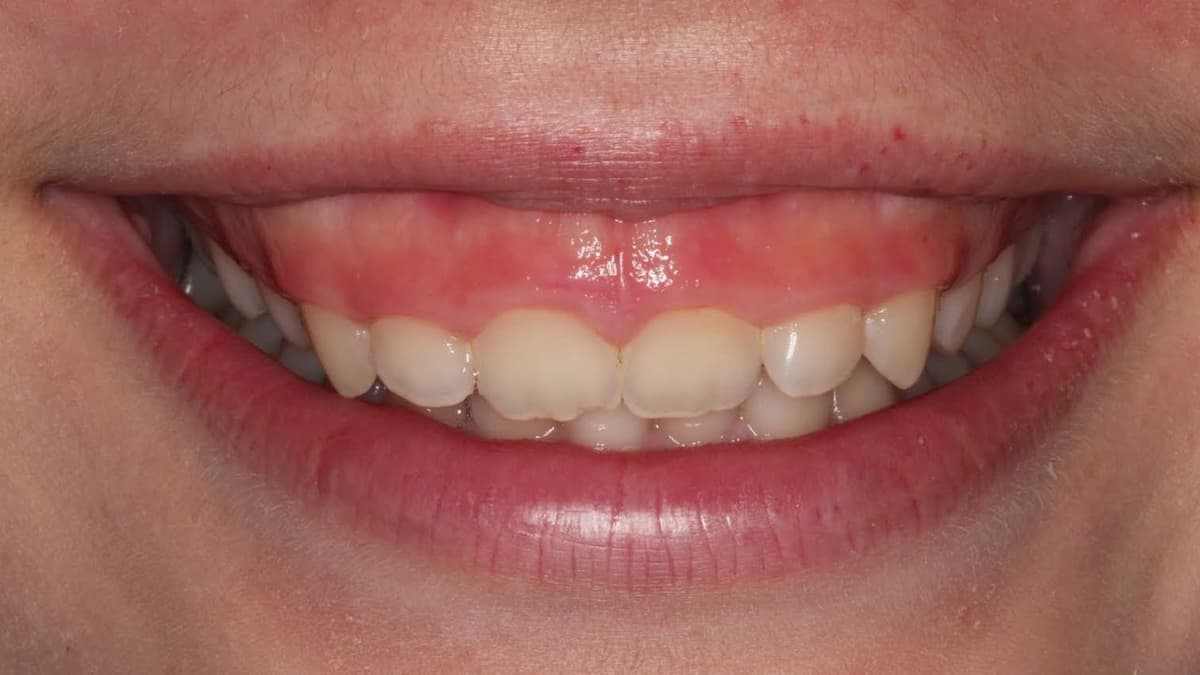

Mức giá phẫu thuật cắt lợi dành cho ai muốn biết

Phẫu thuật cắt lợi là một thủ thuật nha khoa phổ biến, nhằm mục đích điều chỉnh nướu răng để cải thiện sức khỏe răng miệng hoặc nâng cao tính thẩm mỹ của nụ cười. Quy trình này thường được áp dụng cho những người gặp vấn đề về lợi dư thừa, tụt lợi, hoặc […]